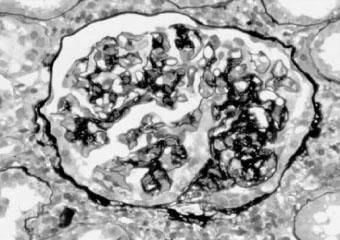

第Ⅰ型:基底膜增厚,并因系膜细胞及基质长入基底膜与内皮细胞间而呈双轨现象,双轨之形成是由插入的系膜形成伪基底膜所致,本型之系膜增生最为严重,可分隔肾小球呈小叶状(图2—9)。电镜检查除系膜插入现象外,并可见细小的不规则电子致密物于系膜区及内皮下,免疫荧光检查可见IgG、IgM及C3颗粒沿基底膜呈周边性分布,也沉积于系膜。

图2—9 系膜毛细血管性肾小球肾炎,基底膜增厚,系膜增生,呈双轨现象(PASM x400)